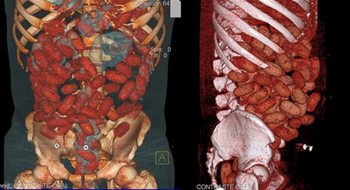

Cảnh sát Brazil vừa phát tán h́nh ảnh nội soi của một người đàn ông Ireland nuốt hàng tá viên ma túy tổng hợp vào bụng nhằm che mắt cảnh sát để đưa lượng ma túy này sang châu Âu.

Hôm thứ 6 (16/9), cảnh sát Brazil đă bắt một người đàn ông 20 tuổi tại sân bay Congonhas khi anh ta đang cố gắng lách qua lực lượng hải quan Brazil để bay tới Brussels với 72 viên ma túy tổng hợp trong bụng.

Những bức ảnh nội soi cho thấy có đến 72 viên ma túy tổng hợp (khoảng 830g ma túy) trong bụng anh ta.

Các h́nh ảnh nội soi của người đàn ông này được cảnh sát Brazin phát tán. Ảnh: The Sun

Người đàn ông đă được đưa đến bệnh viện để lấy số ma túy ra khỏi người. Được biết, lượng ma túy này tương đương với số tiền khoảng 150.000 euro (khoảng 4,3 tỉ đồng Việt Nam).